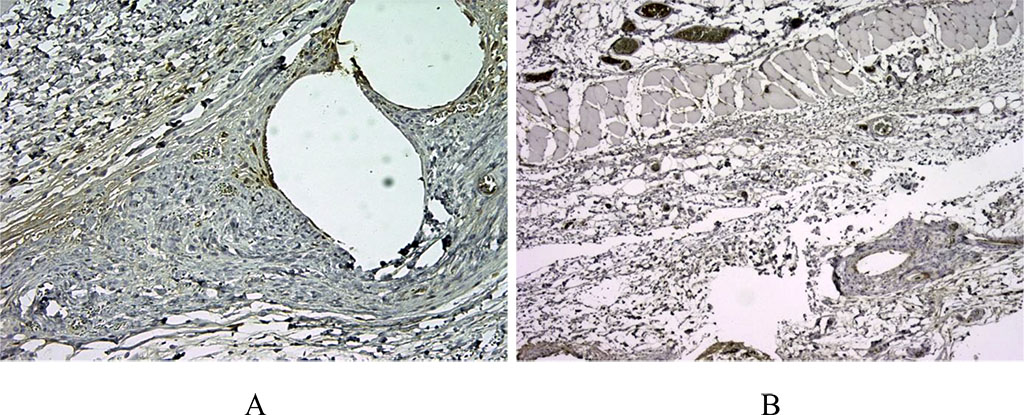

Figure 1. 14 days after implantation, a pronounced lymphoplasmacytic infiltration was noted in the first group. There are many CD3+ cells in this zone, about >60% of the inflammatory infiltrate around the voids – the locations of polypropylene monofilaments (A). In the second comparison group with the use of a bioimplant, we noted a weaker CD3 staining, which indicated a moderate inflammatory response (B). (X100).

There was no statistical difference in the indicators (p≥0.05). On the day 14 after the surgery, a different level of CD3+ expression was noted. Thus, in the first group, a pronounced level of expression of cells around the polypropylene implant was noted, while in the second group, a moderate level of expression was registered (p≤0.05).